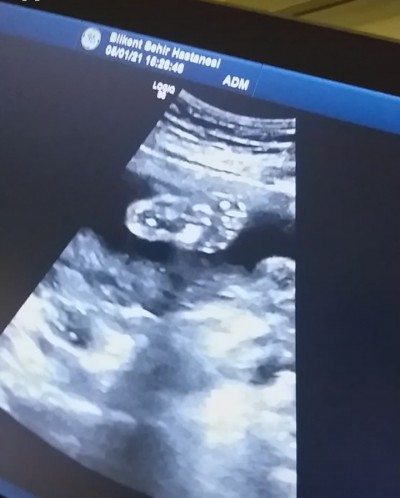

Kızlar bugün ayrıntılı ultrasona gittim bebegimin ayaginin resmini çektim banada resim olarak bebişimin pipisinin resmini verdi doktor hanım:)))

resim çok net olmamış ama gorebildigim kadariyla bitanesi burda

Goruntude govdesi ve kafasi var cok yakindan cektigi icin bacaklarini almamis

Dikkatli bak sadece ayagi ve ayak parmakları var:)) paşamın

Anlayasiya uğraştım ama ben net gordum